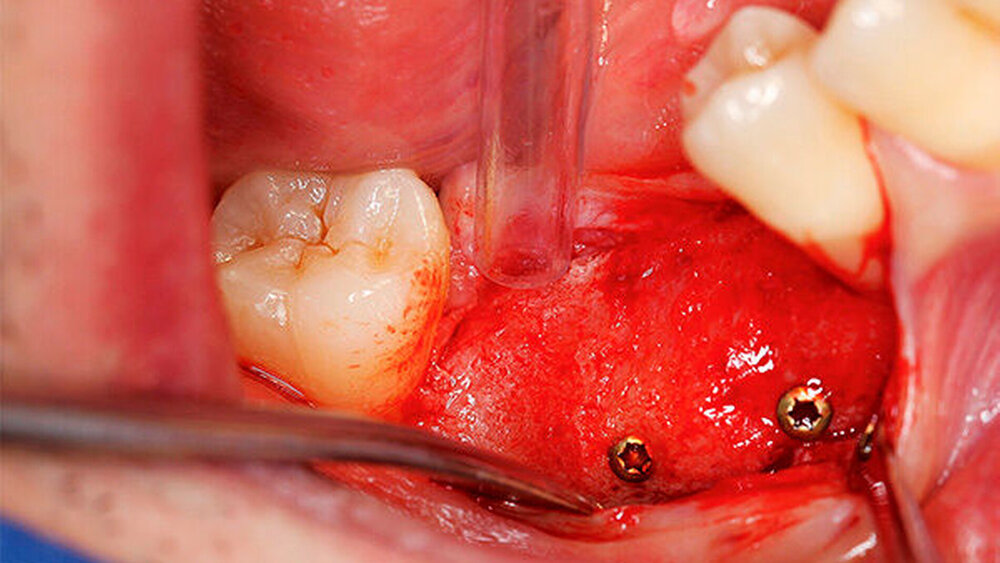

Die Schnittführung wurde nach dem Pillar-Sockel-Design (Blume) vorgenommen. Dabei liegt die Inzision weit im Vestibulum und verbindet zwei vertikale Entlastungsschnitte. Im Gegensatz zu der herkömmlichen krestalen Schnittführung bleibt das Periost über dem augmentierten Bereich damit völlig intakt. Nach der streng subperiostalen Präparation erfolgte die Kontrolle der Passung des CAD/CAM-Blocks. Ein ganz entscheidender Punkt ist, vor jeglichem Kontakt des Blockes mit Blut diesen in steriler Kochsalzlösung und am besten in der PRF-Flüssigkeit zu wässern, sodass sich keine Poren des Blocks mit Blutkoageln verschließen und innerhalb des Blocks ein nicht mit Blut gefüllter Hohlraum bildet. Vor der Befestigung des Blocks wurde die Kompakta des Empfängerbetts mit einer kleinen Kugelfräse mehrfach perforiert um sogenannte Bleeding Points zu setzen, die die Durchblutung des Knochenblocks gewährleisten. Mit zwei Osteosyntheseschrauben mit dem Durchmesser 1,5 mm und der Länge 9 mm wurde der allogene Knochenblock rotationssicher fixiert. Das Augmentat wurde mit einer dünnen Schweinepericard-Membran (Jason membrane, botiss biomaterials GmbH, Vertrieb Straumann) und der PRF-Membran abgedeckt. Der spannungsfreie Wundverschluss erfolgte mit der modifizierten vertikalen Matratzennaht nach Laurrell mit resorbierbarem Nahtmaterial (Vicryl 4.0). Postoperativ wurde ein Oberkiefer-DVT angefertigt. Die Nahtentfernung wurde im Rahmen der Nachsorgeuntersuchung sieben und 14 Tage postoperativ vorgenommen. Nach einer Heilzeit von sechs Monaten erfolgte die Implantation in Lokalanästhesie unter antibiotischer Abschirmung mit 2 g Amoxicillin oral eine Stunde präoperativ. Die Schnittführung erfolgte krestal, und nach subperiostaler Präparation wurde der Knochenblock dargestellt und die Osteosyntheseschrauben wurden entfernt. Danach wurden drei Implantate (Straumann) in den Knochenblock gesetzt und mit 0er-Verschlussschrauben abgedeckt. Die Wundrandadaptation erfolgte mit resorbierbarem Nahtmaterial, das bei der Verlaufskontrolle sieben Tage postoperativ vollständig entfernt wurde. Nach dreimonatiger gedeckter Einheilung wurden die Implantate im Rahmen einer Vestibulumplastik freigelegt. Dafür wurde eine erneute krestale Schnittführung regio 14 bis 17 vorgenommen und ein Splitflap präpariert. Der vestibuläre Wundrand wurde mit Einzelknopfnähten im Vestibulum fixiert. Im Bereich der Implantate wurde der Splitflap perforiert, um die Abdeckschrauben gegen Gingivaformer auszutauschen, und der Bereich des nun freiliegenden Bindegewebes wurde mit einer 3D-vernetzten Kollagenmatrix (mucoderm, botiss biomaterials GmbH, Vertrieb Straumann) abgedeckt. Diese wurde zunächst gewässert, um die Verarbeitung zu erleichtern, und an den Stellen der Gingivaformer gestanzt. Die Nahtentfernung erfolgte neun Tage postoperativ. (Abb. 1a bis 1f).

Ein 29-jähriger Patient stellte sich mit einer massiven Alveolarkammatrophie im rechten Unterkiefer in unserer Praxis vor. Diese lag in langen Jahren der Zahnlosigkeit begründet. Eine Beckenkammaugmentation kam für den Patienten nicht in Betracht. Dennoch wünschte er die Versorgung mit festsitzendem Zahnersatz. Nach ausführlicher Beratung entschied sich auch dieser Patient für eine Augmentation mit einem patientenindividualisierten allogenen CAD/CAM-gefertigten Knochenblock. Die DICOM-Daten des Unterkiefer-DVTs wurde an die Firma Zimmer gesendet, und es erfolgten wie im oben beschriebenen Fall eine virtuelle Planung und das virtuelle Design des allogenen Knochenblocks anhand der geplanten Implantatpositionen. Nach der üblichen Kontrolle und Freigabe des Chirurgen erfolgte die eigentliche Fertigung und Übersendung des Knochenblocks in die Praxis. Die Augmentation erfolgte auch in diesem Fall in Vollnarkose unter antibiotischer Abschirmung perioperativ mit Ampicillin. Die Schnittführung im Unterkiefer unterscheidet sich von der Sockelschnittführung im Oberkiefer aufgrund der Anatomie (N. mentalis). Auch bei diesem Patienten wurde eine tief im Vestibulum liegende bogenförmige Inzi‧sion durchgeführt, jedoch ohne die vertikalen Entlastungen. Nach streng subperiostaler Präparation erfolgte die Darstellung des N. mentalis. Die Vorbereitung des Spenderbetts sowie die Wässerung, Einpassung und Befestigung des allogenen Knochenblocks gestalteten sich wie im Fallbeispiel 1. Die Heilzeit des Knochenblocks dauerte ebenfalls sechs Monate. Zwei Implantate (Straumann) wurden nach krestaler Schnittführung in Lokalanästhesie eingebracht und heilten subgingival binnen drei Monaten ein. Aufgrund des massiven Volumenzuwachses war auch ebenfalls eine Vestibulumplastik im Zuge der Implantatfreilegung notwendig. Das Prozedere verlief ebenfalls wie im Fallbeispiel 1. Das freiliegende Gewebe wurde mit einer Kollagenmatrix abgedeckt. Dadurch konnte die Breite der befestigten Gingiva deutlich verbreitert werden.